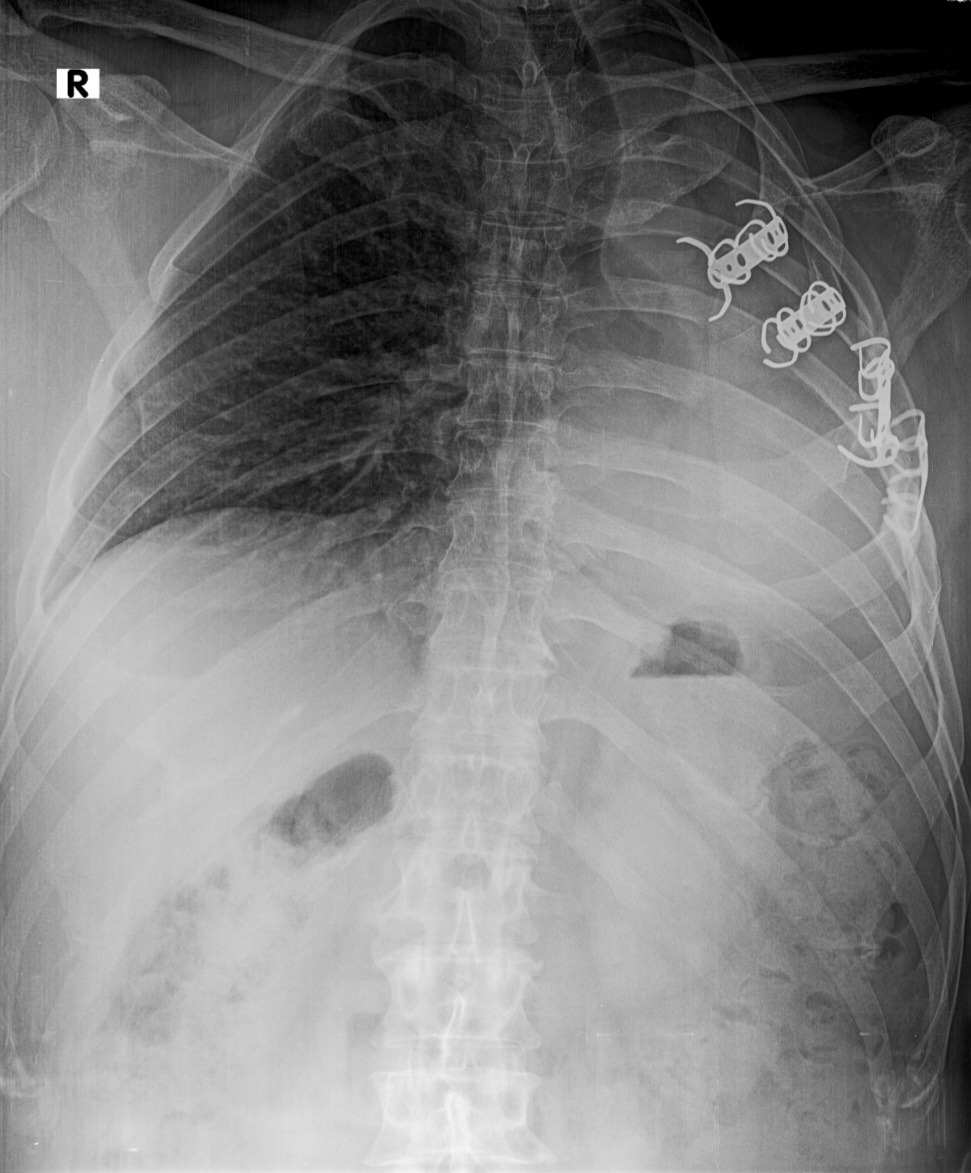

We are asking for help to pay for a surgery for david giesbrecht from cuauhtemoc chihuahua campo 13A he had a accident 4 years ago and he broke his ribs and damage his lungs and the surgery didn't fall out good and now he needs a surgery again and they don't really have money so anything helps and he can't work so they have only 2 girls working and they don't make much .it's also translated to Spanish

Estamos pidiendo ayuda para pagar una cirugía para david giesbrecht de cuauhtemoc chihuahua campo 13A tuvo un accidente hace 4 años y se rompió las costillas y se dañó los pulmones y la cirugía no le cayó bien y ahora necesita una cirugía nuevamente y realmente no tienen dinero así que todo ayuda y no puede trabajar así que solo tienen 2 hijas trabajando y no ganan mucho